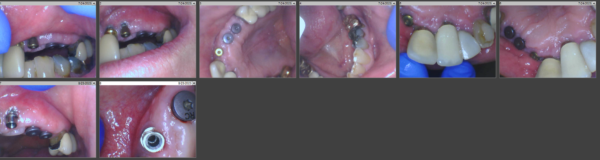

Dustin started the discussion Healing complication in the forum Complications 2 years ago

Hello. I placed an implant in site #28 on 25 y/o male. Pt has controlled type 1 diabetes. recent A1C 5.8. Otherwise healthy. Placed with good initial stability and cover screw placed and resorbable sutures. Pt did not return for any follow ups and did not return any check up phone calls. He scheduled 2nd stage prior to surgery and showed up…